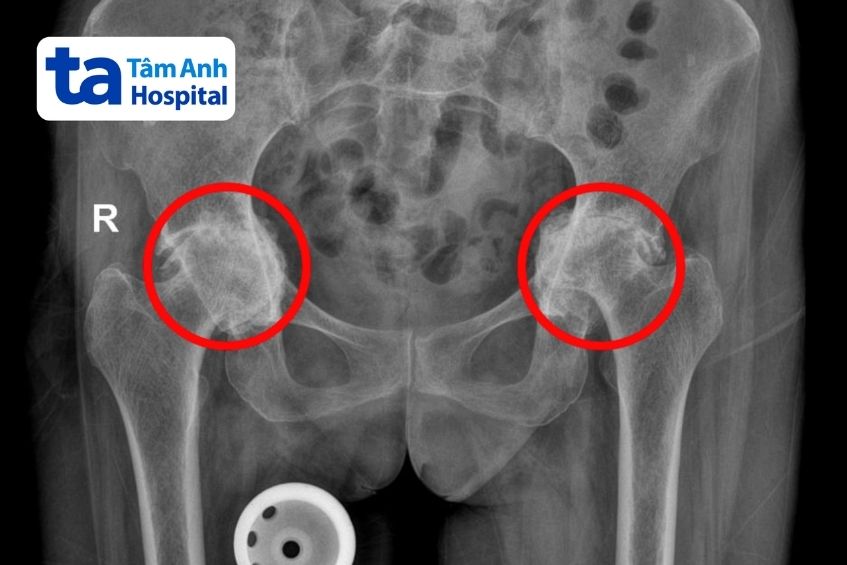

Kết quả chụp X-quang tại Bệnh viện Đa khoa Tâm Anh TP HCM cho thấy sụn ở hai bên khớp gối của người bệnh đã bị mài mòn hoàn toàn và tiêu biến. Trong khi đó, khớp háng hai chân thoái hóa nặng, chỏm xương đùi lệch khỏi vị trí bình thường, chui vào trong ổ bụng.

Người bệnh được tiến hành hay khớp háng trái sau đó sáu tháng, thời gian đủ để bình phục sức khỏe sẵn sàng cho ca đại phẫu tiếp theo. Theo bác sĩ Khoa, thách thức lớn nhất lúc này là người bệnh đã bị viêm thoái hóa lâu ngày dẫn đến tình trạng chỏm xương đùi di lệch vào trong nhiều, mất nền xương ổ cối. Nếu không tính toán chính xác lượng xương cần bù và hướng đặt khớp nhân tạo, sau mổ, khớp mới có nguy cơ lọt thẳng vào trong ổ bụng, giảm tuổi thọ khớp, trật khớp háng.